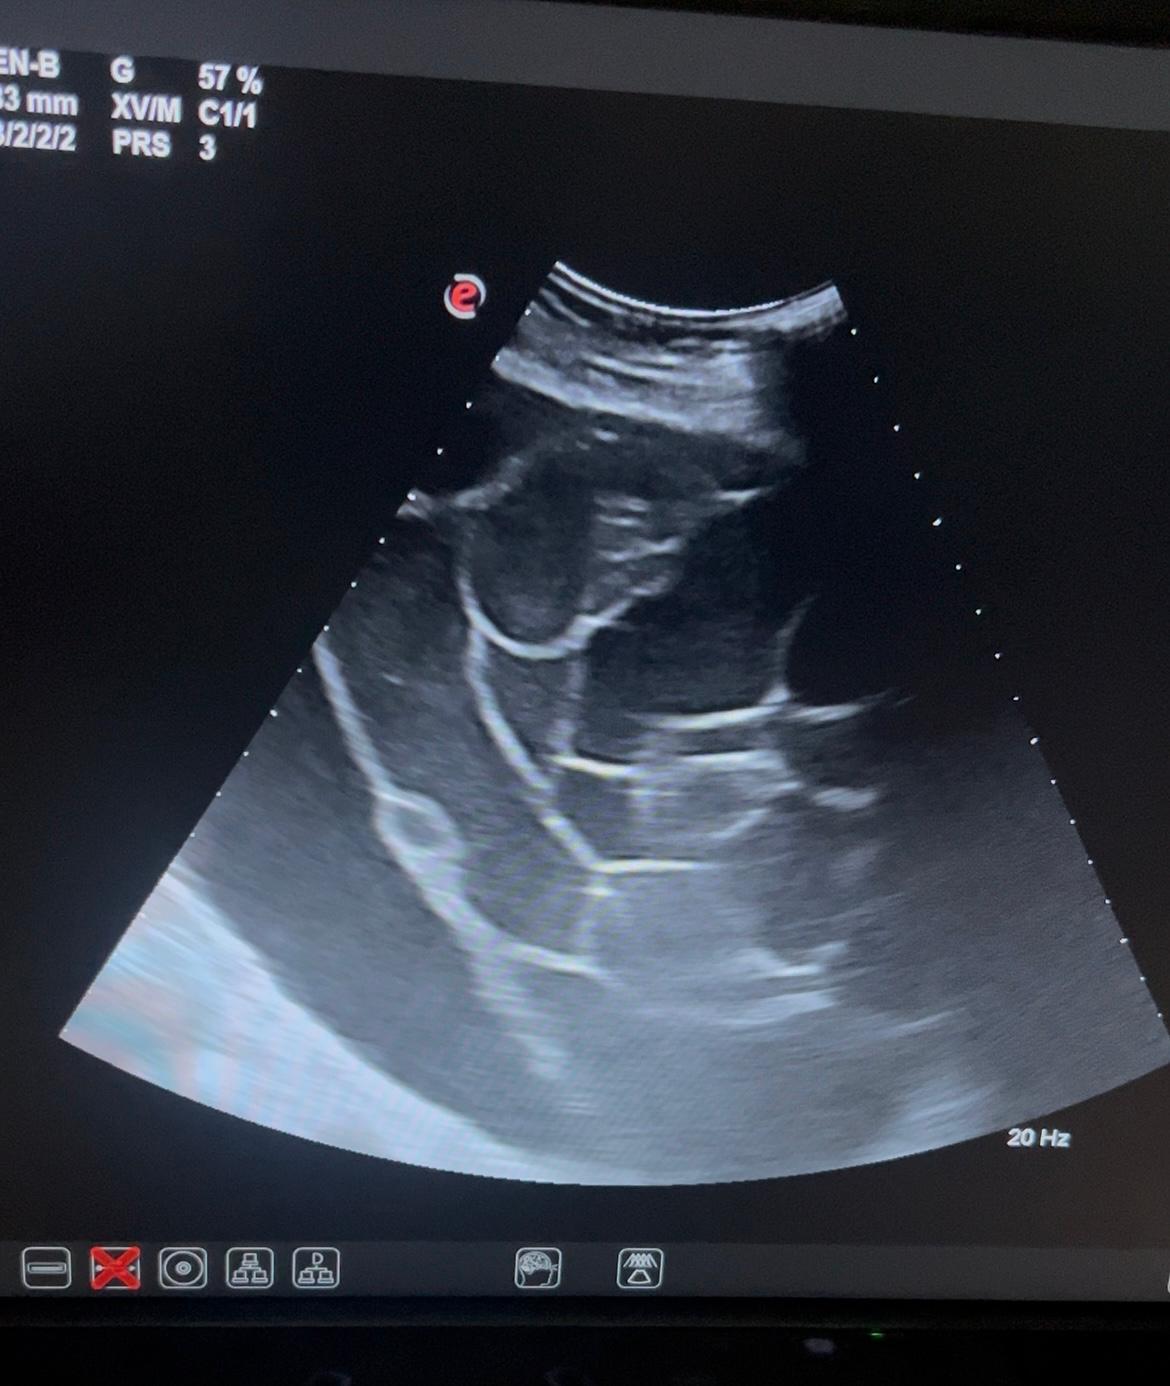

Ante la clínica discordante con la exploración procedemos a la ecografía abdominal en consulta.

Hallazgos ecográficos

Juicio clínico: tumoración ovárica izquierda a filiar. Sospecha cistoadenoma mucinoso.

Evolución: en urgencias hospitalarias Eco-TV visualizando imagen quística, multiloculada, sin captación de doppler, sin papilas sólidas en su interior, con punteado fino, de 23x12 cm. Solicitan analítica con marcadores tumorales y cita preferente en consulta de masas anexiales.

En consulta de masas anexiales Eco TV: ovario izquierdo aumentado de tamaño a expensas de una lesión multilocular de 24 x 18 cm, con lóculo de mayor tamaño de unos 14 cm. La lesión no presenta tabicaciones gruesas ni lesiones papilares sospechosas, un patrón ecográfico de cistoadenoma mucinoso ovárico GIRADS 3.